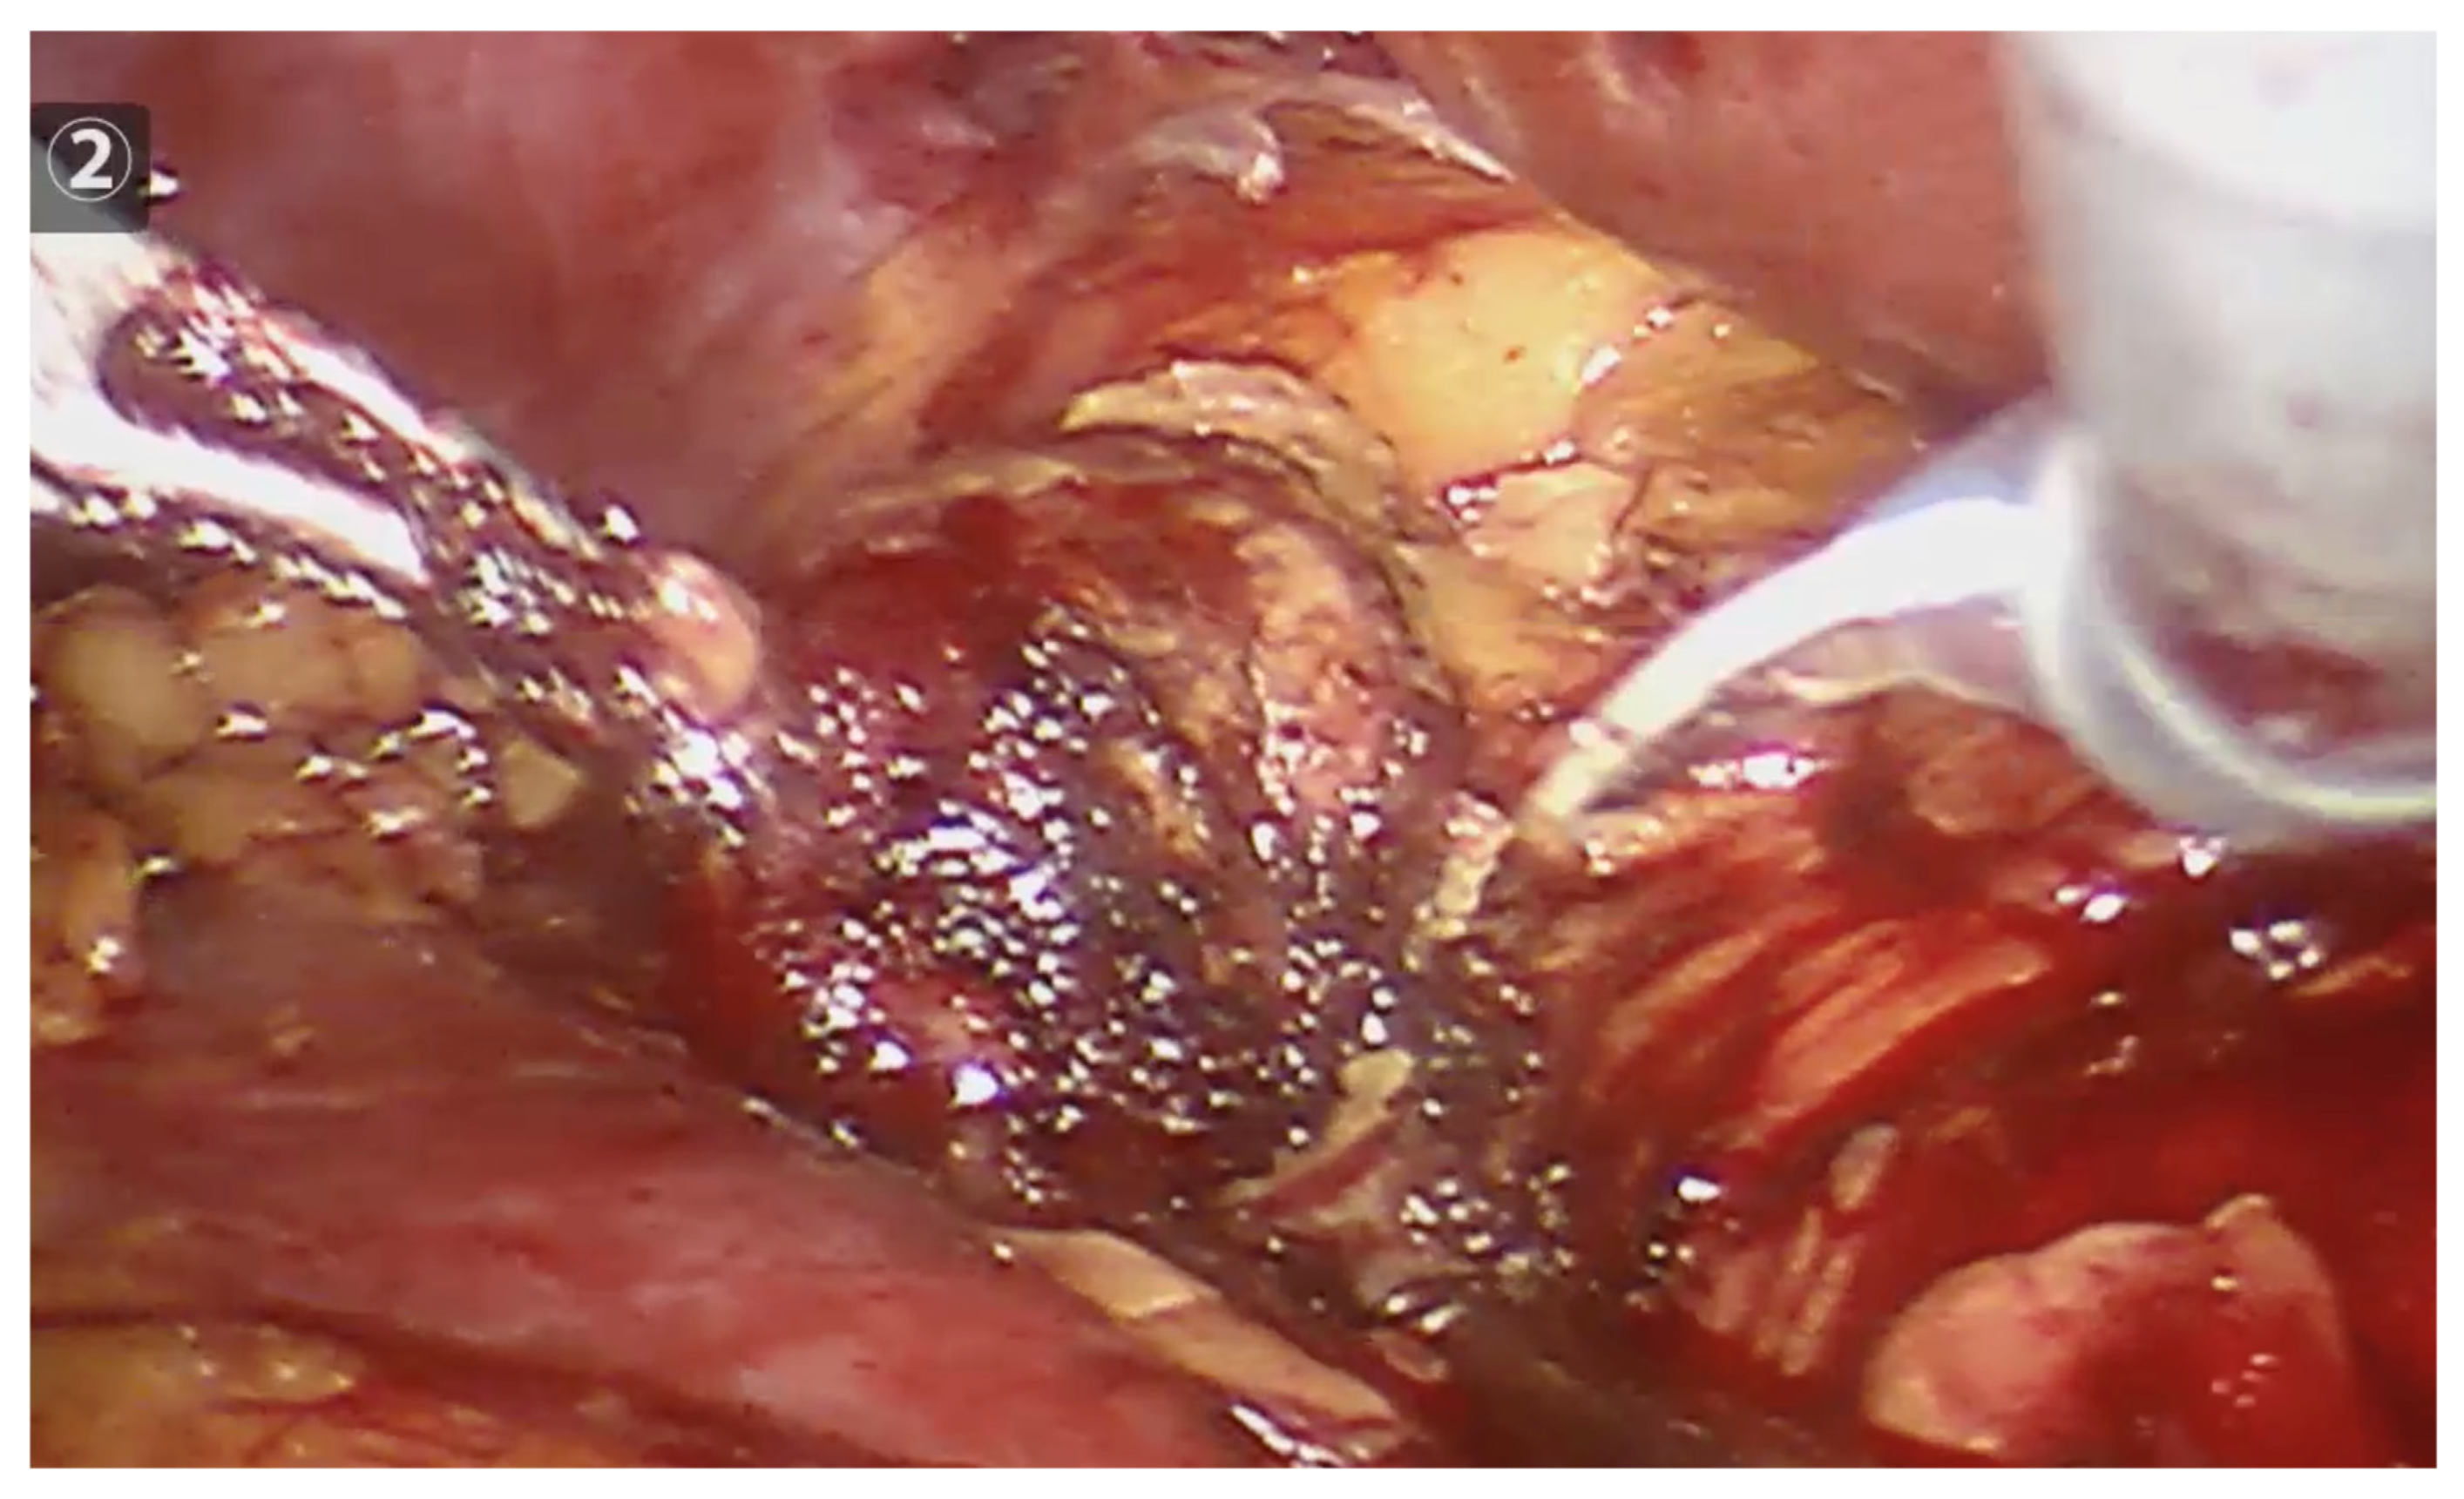

2.2. Procedure and Technique